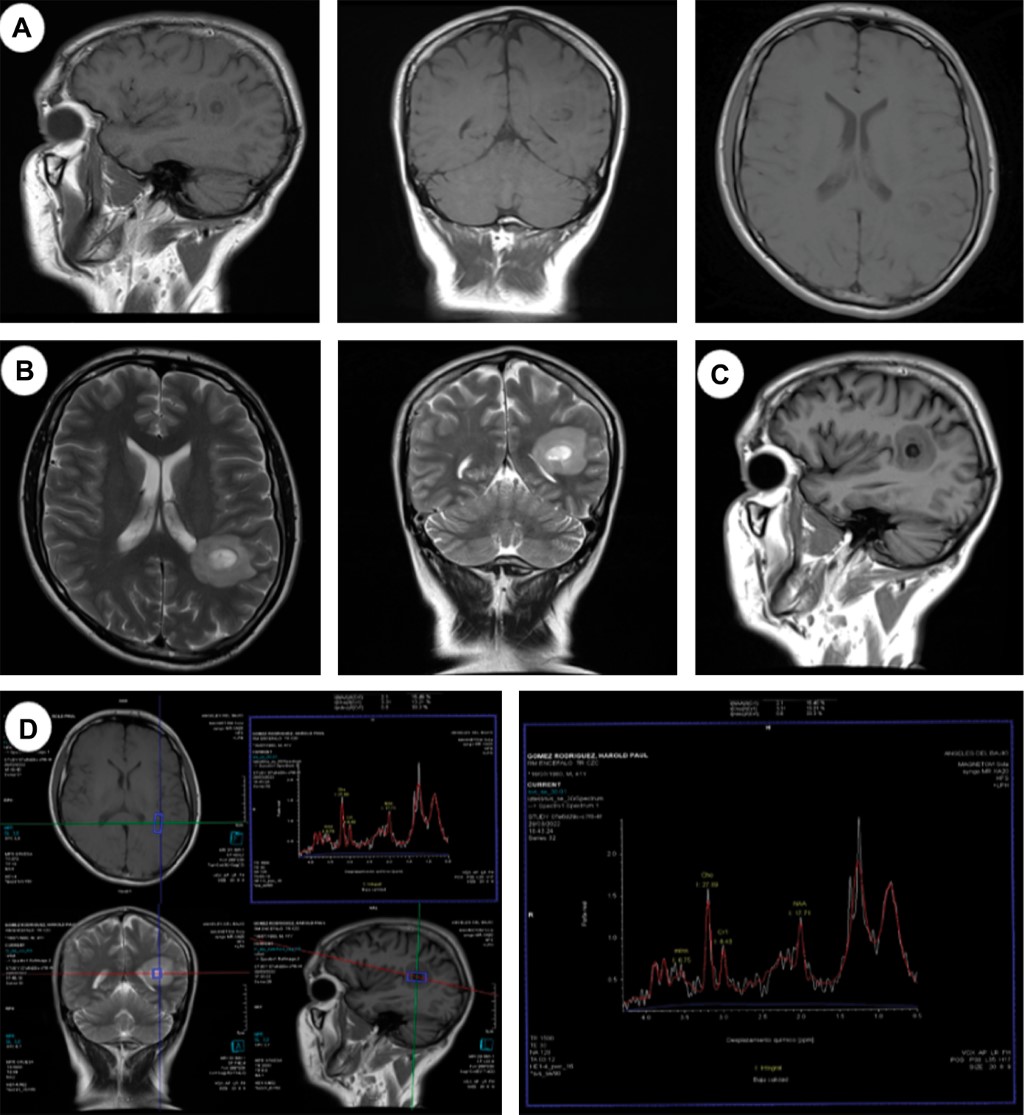

A 41-year-old male patient with a history of traveling to a cave, where he eats raw meat and has poor hygiene conditions. It begins with neurological symptoms, dizziness, dysarthria, difficulty identifying objects, and poor response to medical management. An MRI where a heterogeneous cystic tumor with a mural nodule was found; spectroscopy was performed, showing a lipid peak, suggesting an infectious process. An intervention was performed for stereotaxy, and it was sent to pathology, where they issued us the report of histoplasmosis.

Figure 2